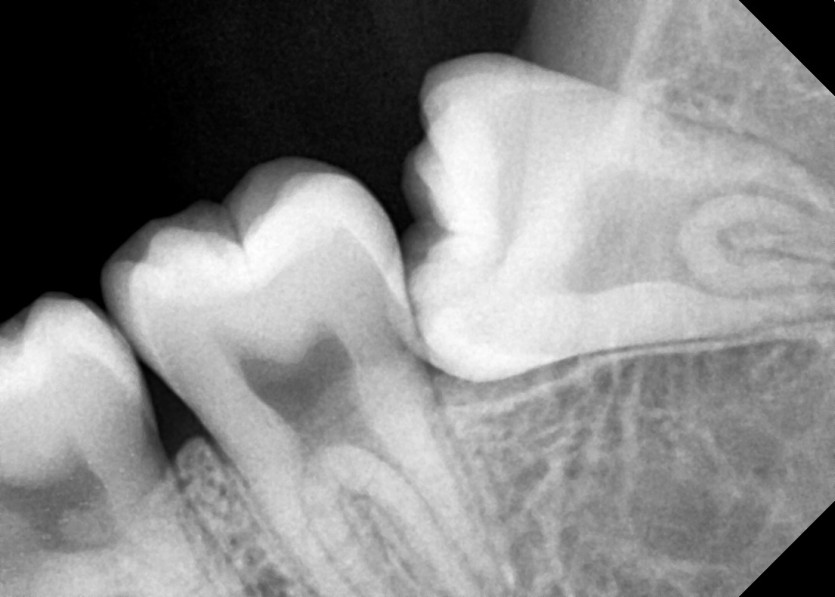

#18,28,38,48 사랑니 발치

구강 외과 전문의가 당일 발치했습니다.